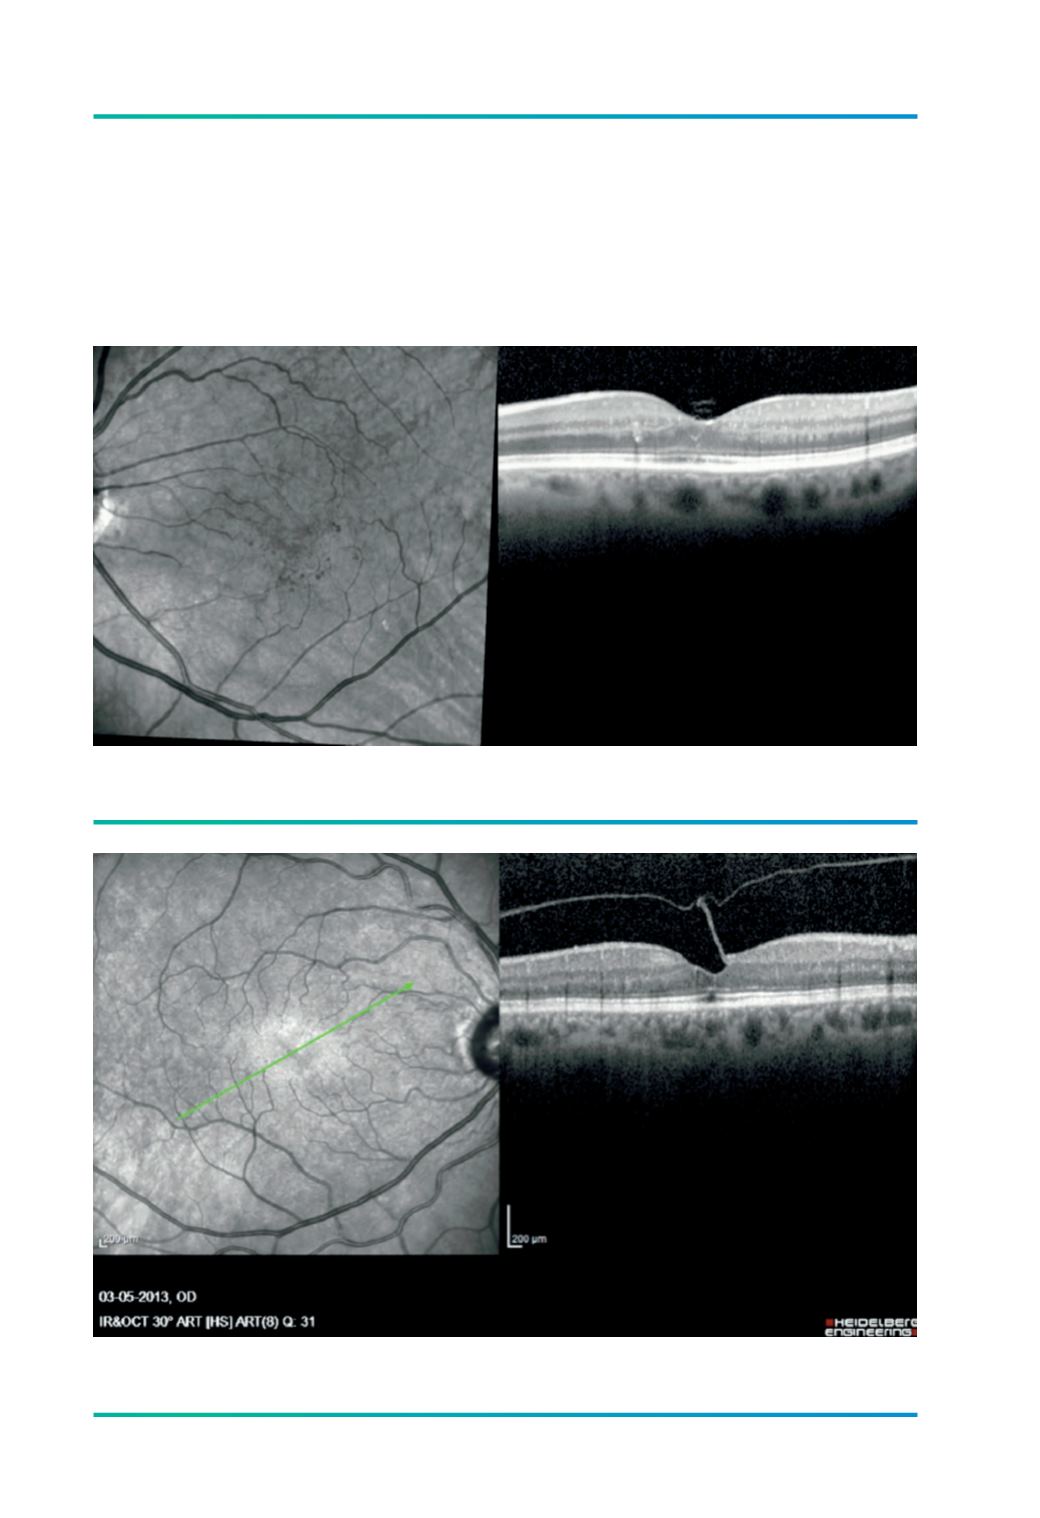

Figura 2.

Libertação espontânea da adesão vítreo-macular numa oclusão venosa após terapêutica com anti-VEGF.

Figura 3.

Tracção vítreo-macular. A hialóide posterior separa-se da retina, mantendo-se parcialmente aderente à fóvea.